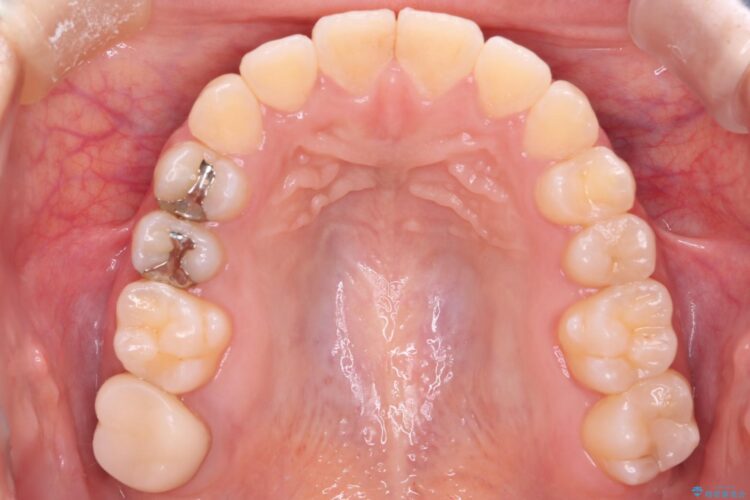

八重歯とガタつきが気になるとご来院された患者様です。

精密検査の結果、抜歯はせずIPR(歯と歯の間を削る処置)を行い、目立ちにくい審美ワイヤー装置にて歯列拡大を行うことで歯列を整える治療計画を立てました。